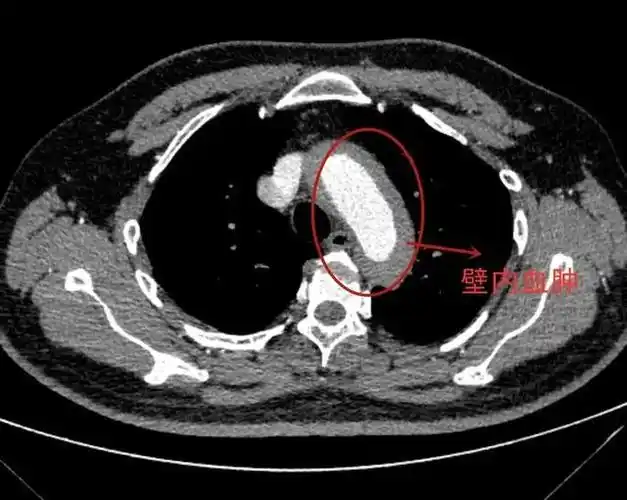

主动脉夹层

主动脉夹层分型